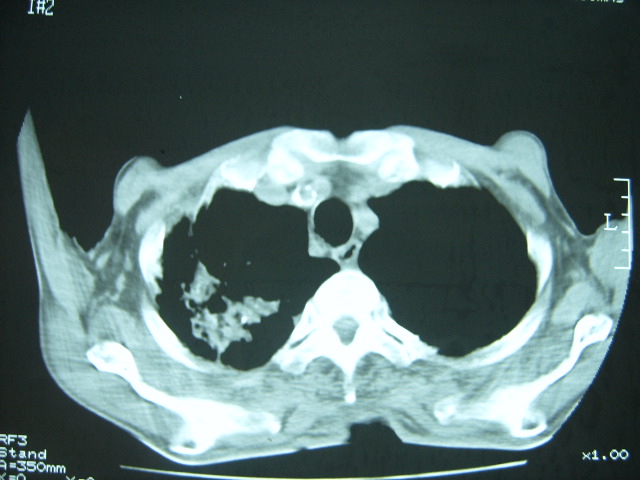

男74岁,咳嗽,寒战,低烧。有糖尿病史。

两肺结核,空洞形成,左下肺肺段隔离症待排

1、左下肺肺脓肿,合并霉菌球形成?.2、双肺陈旧性病灶.3、右上肺病灶警惕瘢痕癌,建议定期复查.

两肺结核,左下肺大片实变,内见空洞性病变,壁不规则,结合糖尿病史,考虑:结核性?霉菌性?建议结合实验室检查或治疗后复查。